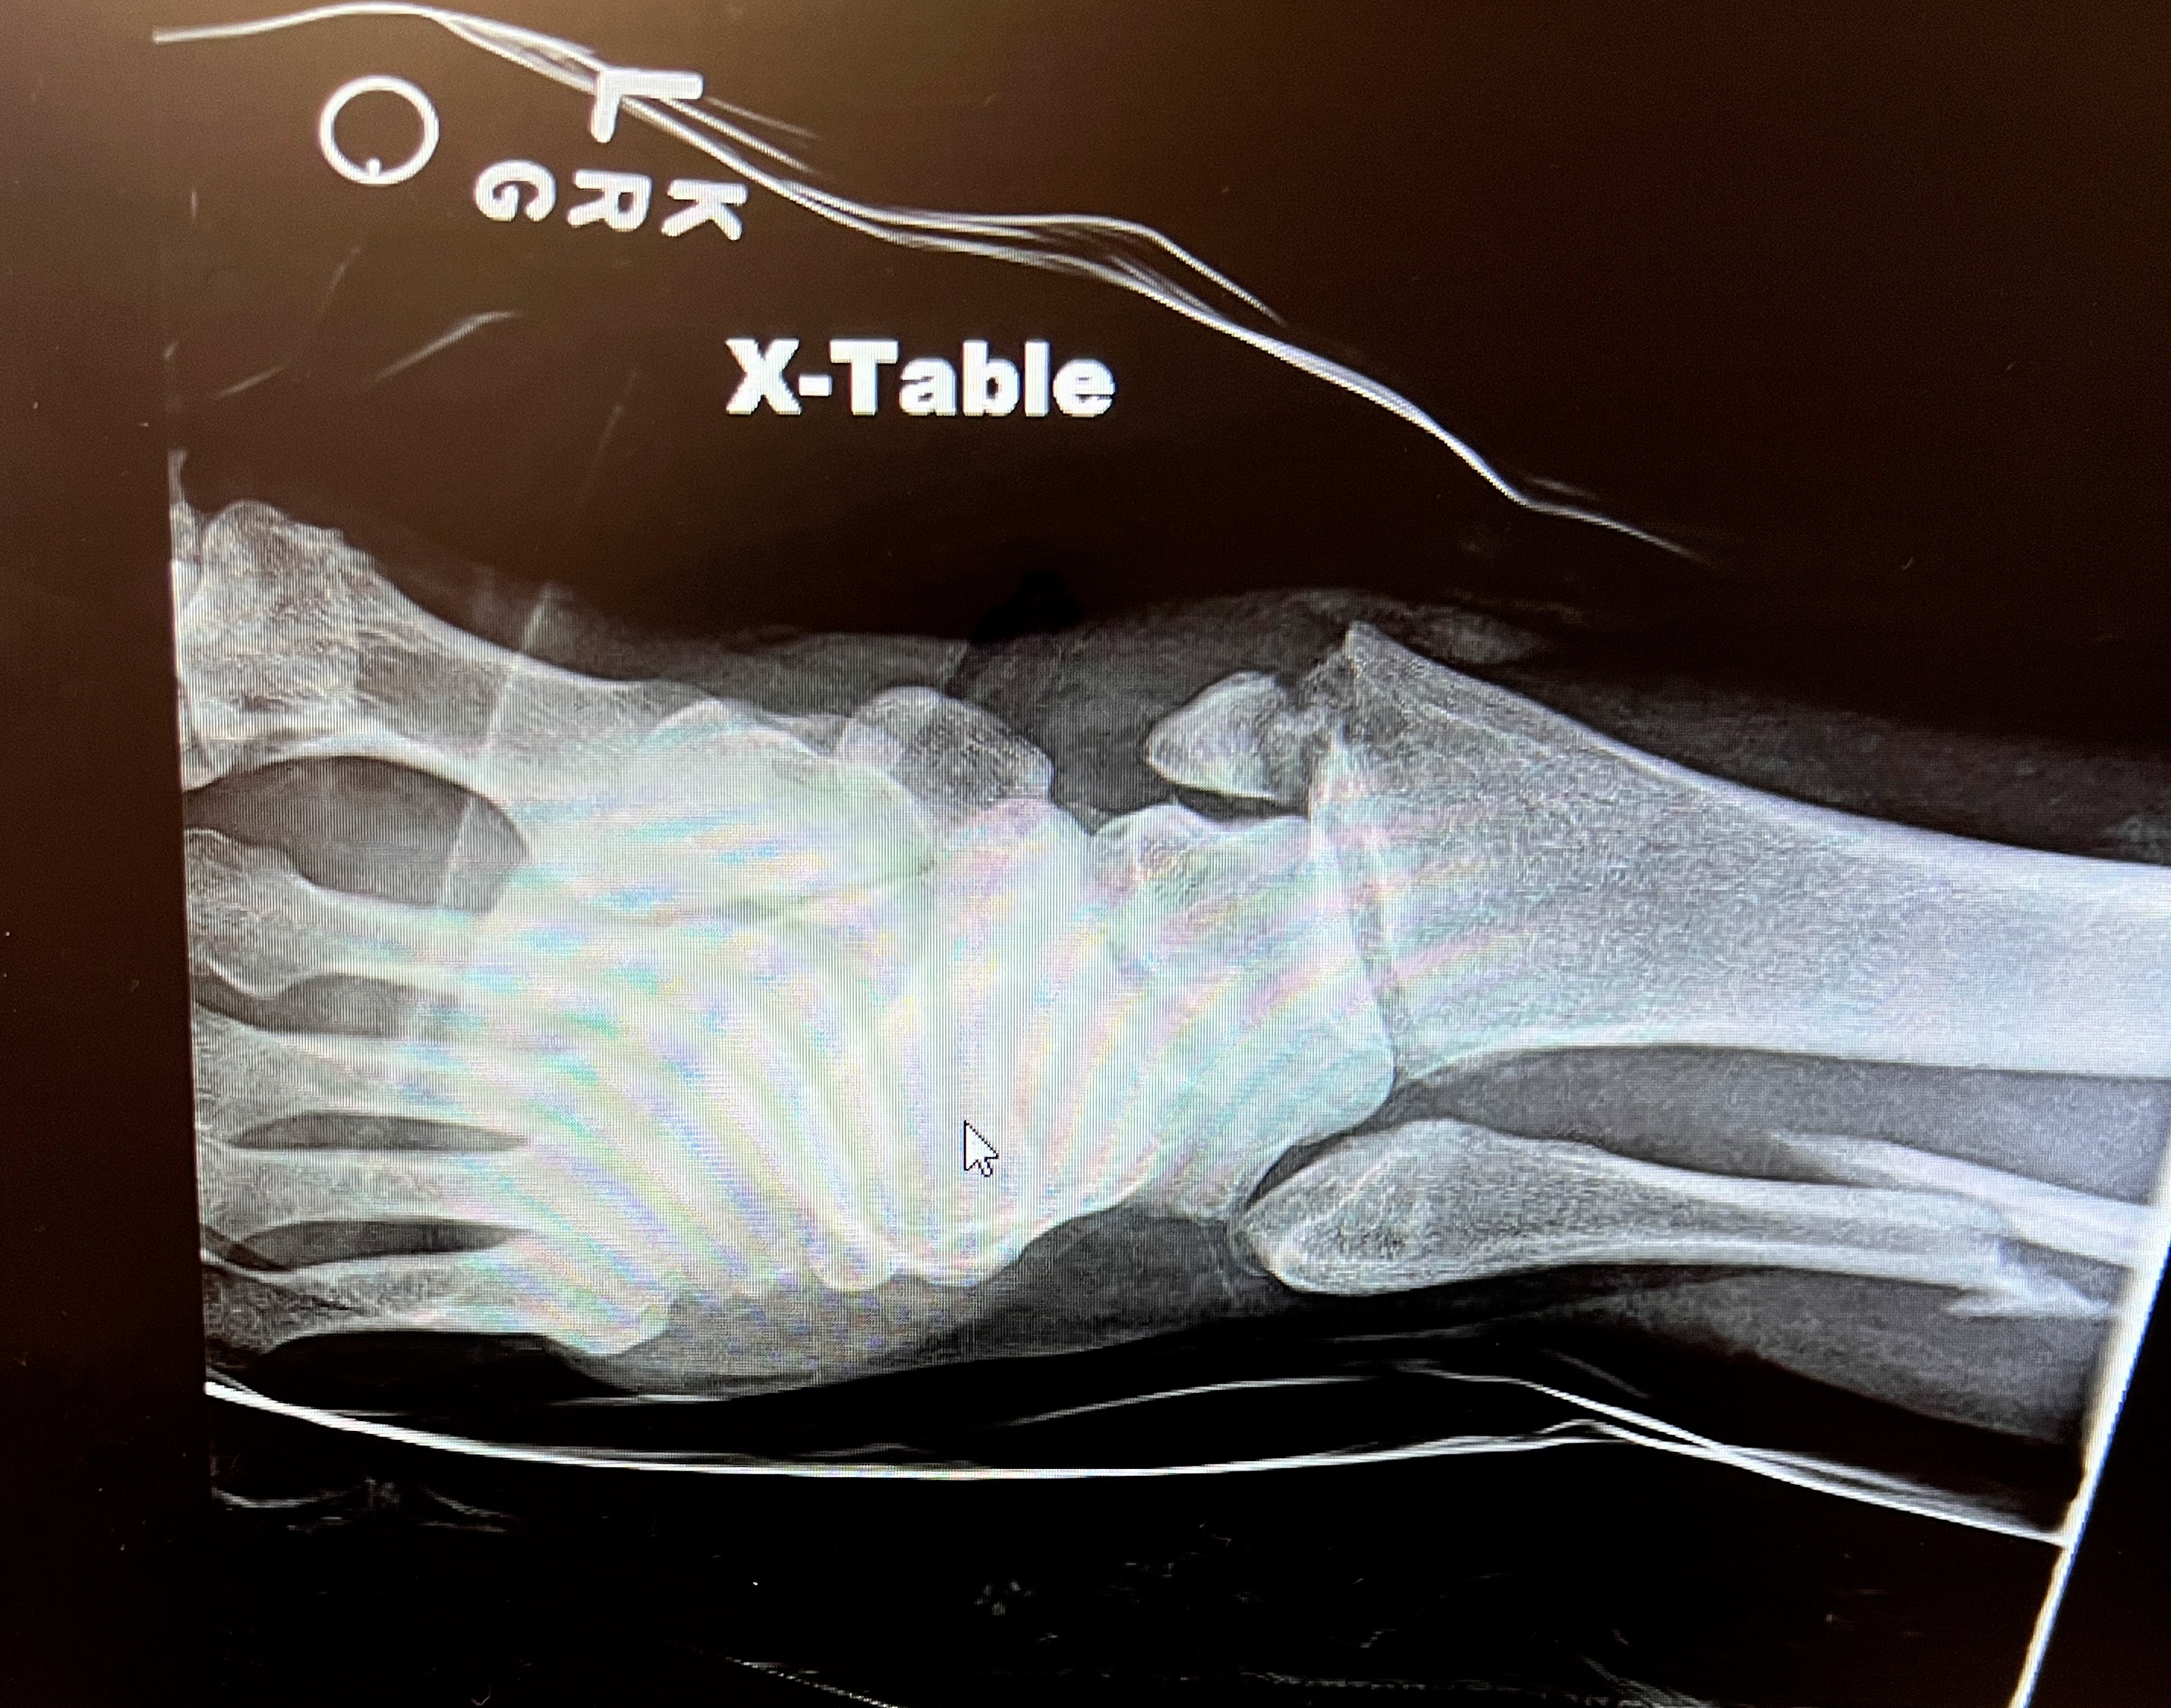

After a while, an x-ray technician took several images of my ankle while I laid on the ER gurney. The x-ray tech was very gentle and apologized when she had to place the plate under my ankle. She then sat down at her mobile x-ray unit station while the images uploaded. I looked over at her as she reviewed the x-rays and noticed her face suddenly change as she unconsciously winced and grimaced when she saw them. I commented lightly to her saying, “Based on your expression, it must not look great.” Her wincing face had cleared then, and she warmly remarked with, “All I can say is that you are really strong!!” I thanked her and received that confirmation fully. Looking at the x-rays myself days later, I realized why she had winced. My fibula bone on the outer side of my left leg was completely severed. Looking at that made my stomach churn for a moment when I actually saw it many days later.

On Thursday afternoon April 17, 2025, I had my second and final successful ankle surgery at UNM Hospital. Dr. Wharton and his team installed all the internal hardware to support the healing of my three fractured bones. I did indeed feel like the Bionic Woman after I saw the x-rays days later. My husband managed through some hours of worry as my procedure started late and the orthopedic team did not update him promptly when I was out of surgery. He was grateful to join me when they wheeled me to my hospital room. We were both thankful to learn that the surgery went really well.